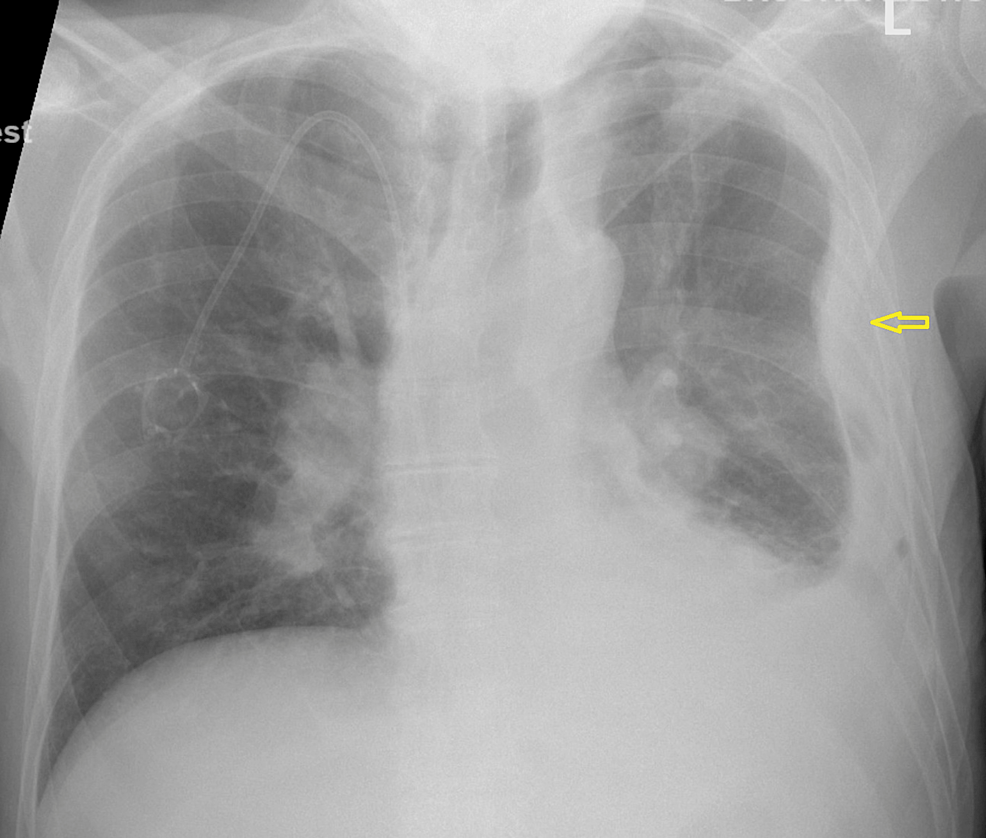

Loculated Effusion Chest X Ray . No other specific radiographic features are seen. On the image, loculated pleural effusion may. Chest radiography can confirm the diagnosis. Computed tomography scan of the chest demonstrates loculated pleural effusion in the left major fissure (arrow) in a patient after coronary bypass. Dullness to percussion on physical examination suggests an effusion; Out of concern for malignancy, exploration of. Obliteration of left costophrenic angle with a wide pleural based dome shaped opacity projecting into the lung. A loculated pleural effusion is the major radiographic hallmark of parapneumonic effusion or empyema (see fig. Patient presented with fever and chest pain since last 7 days.